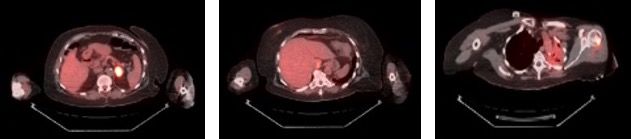

Six months following her surgery, a routine annual screening mammogram revealed 2 new adjacent nodules in the lower central right breast suspicious for breast cancer (Figure 3). Ultrasound guided biopsy of these lesions revealed adenocarcinoma consistent with metastasis from lung primary (Figure 4). A restaging PET-CT scan revealed new hypermetabolic lesions involving caudate lobe of liver, left adrenal gland, and bone lesions in left humerus, right scapula, and right ischium, which were totally asymptomatic (Figure 5).

Figure 5. New PET-CT scan. New positive areas of F-18 fluorodeoxyglucose uptake in the left adrenal gland, caudate lobe of the liver, and left humerus. Vague, minimal uptake in the left lung was thought to be pneumonitis.